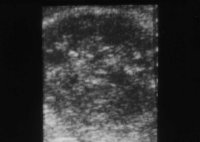

In der Diagnostik der Nierenabszesse (intra- bzw. peri/paranephritisch) spielen neben der Anamnese, Symptomatik (Fieber, Flankenschmerzen) die Laboruntersuchungen: Entzündungsparameter wie BSG und CRP, Kreatinin und Elektrolyte sowie der Urinstatus eine Rolle.

Von Wichtigkeit sind die bildgebenden Verfahren: Sonographie, CT bzw. AUR.

Beispielhaft die Darstellung eines ausgedehnten Nierenabszesses in Sonographie, CT und AUR (Abbildung 6).

Die Abbildung zeigt als weiteres Beispiel die sonographische Darstellung eines ausgedehnten paranephritischen Abszesses (Abbildung 7).